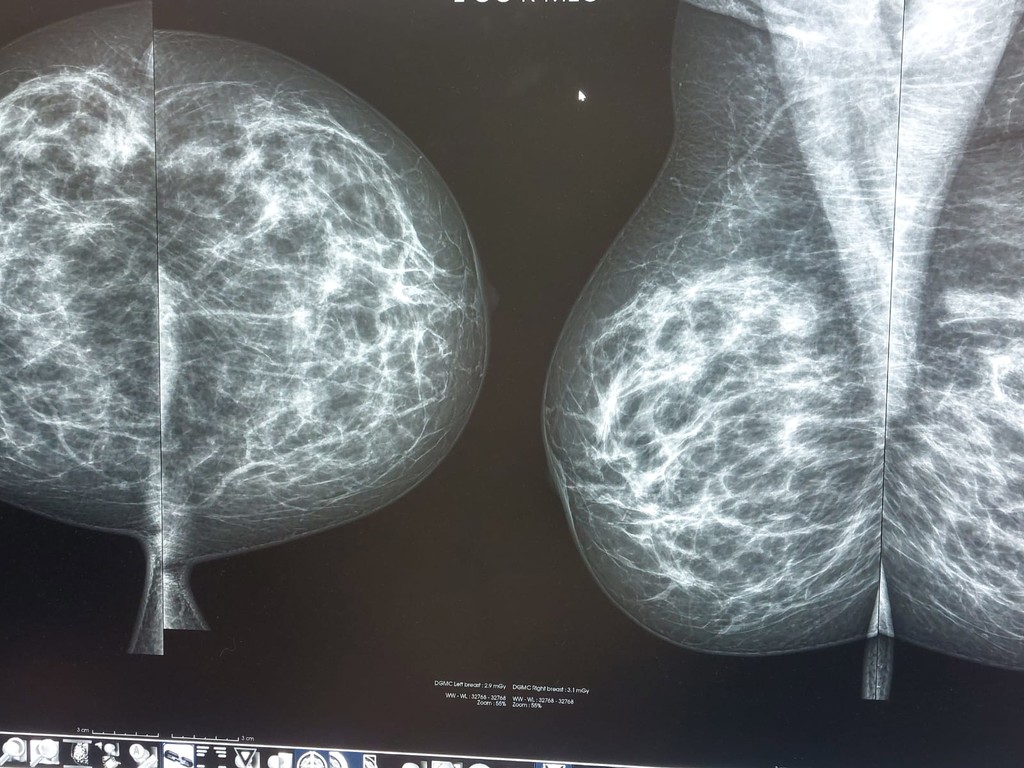

La raffineria Sarpm sostiene il progetto Carovana della Prevenzione e offre una giornata di promozione della salute con visite specialistiche per la prevenzione dei tumori del seno riservate alle donne fuori screening regionali (mammografia per donne fra i 40 e i 49 anni e over 70 e ecografia senologica under 40) residenti nel Comune di Quiliano.